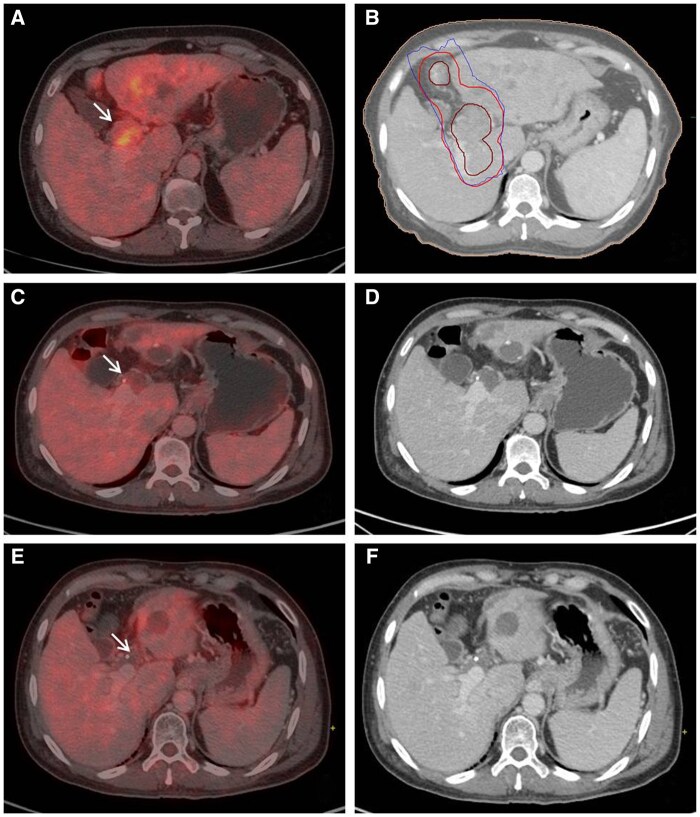

Methods: The present retrospective study included 24 patients without extrahepatic metastases. The patients had received drug eluting beads - transarterial chemoembolization (DEB-TACE) (n = 10) and systemic treatment (n = 14) before RT. The dose fractionation was 12-31.5 Gy in 3-7 fractions of 4-5 Gy to PVTT or PVTT plus the liver parenchymal tumour. All patients were advised systemic treatment with sorafenib, lenvatinib, or nivolumab after RT. After RT, patients had received DEB-TACE within 8 weeks (n = 2) or at 5-10 months (n = 3). Treatment response was evaluated as per mRECIST and PERCIST, and Kaplan-Meier survival analysis was performed.

Results: The disease control rate in PVTT was 50% at 3 months. The median overall survival (OS) was 10.9 months (95% CI, 0.74-21) for all patients. The 6-month, 1-year, 2-year, and 3-year OS rates were 75%, 45.8%, 25%, and 12.5%, respectively. The median OS was 30.4 months (95% CI, 12.1-48.7) versus 18.1 months (0.00-38.8) with complete or partial response versus stable or progressive disease in PVTT (P = .036). Eleven patients had a decline in Child Pugh score of 2 or more points within 3 months after RT. One patient underwent live donor liver transplantation (LDLT) and complete necrosis with no viable tumour was observed in the explant. The patient is cancer- and liver disease-free at 1 year after LDLT.